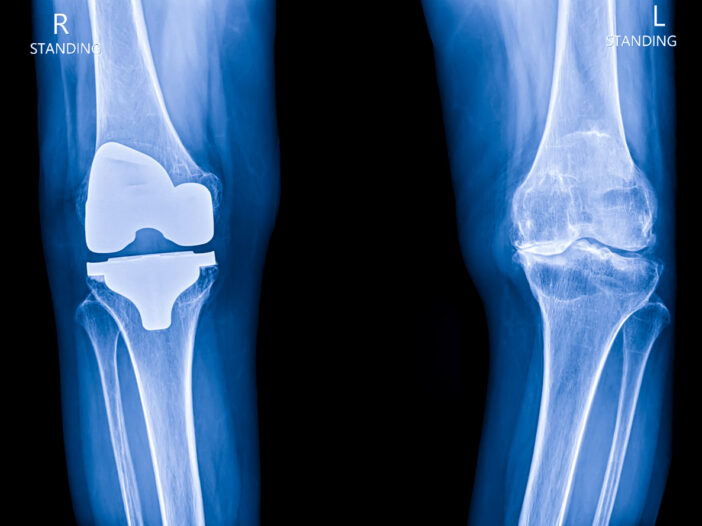

At Central Maine Healthcare, we specialize in total and partial knee replacement, in which an injured or arthritic joint is replaced with state-of-the-art, artificial components. In addition to relieving pain, the knee replacement can restore function and mobility and get you back doing what you need and love to do.

With total knee replacement, damaged cartilage and bone are removed from the knee joint. Specially designed parts, called prostheses, are then placed in the knee. These pieces may be placed in up to three surfaces in the knee joint:

- Lower end of the thigh bone (femur). The replacement part is usually made of metal.

- Upper end of the shin bone (tibia), which is the large bone in your lower leg. The replacement part is usually made from metal and a strong plastic.

- Back side of your kneecap (patella). The replacement part is usually made from a strong plastic.

As an alternative to total knee replacement, we also offer partial knee replacement. This procedure may be an option if your arthritis is confined to one area of the knee, and conservative treatments like physical therapy, medication or weight loss no longer provide relief.